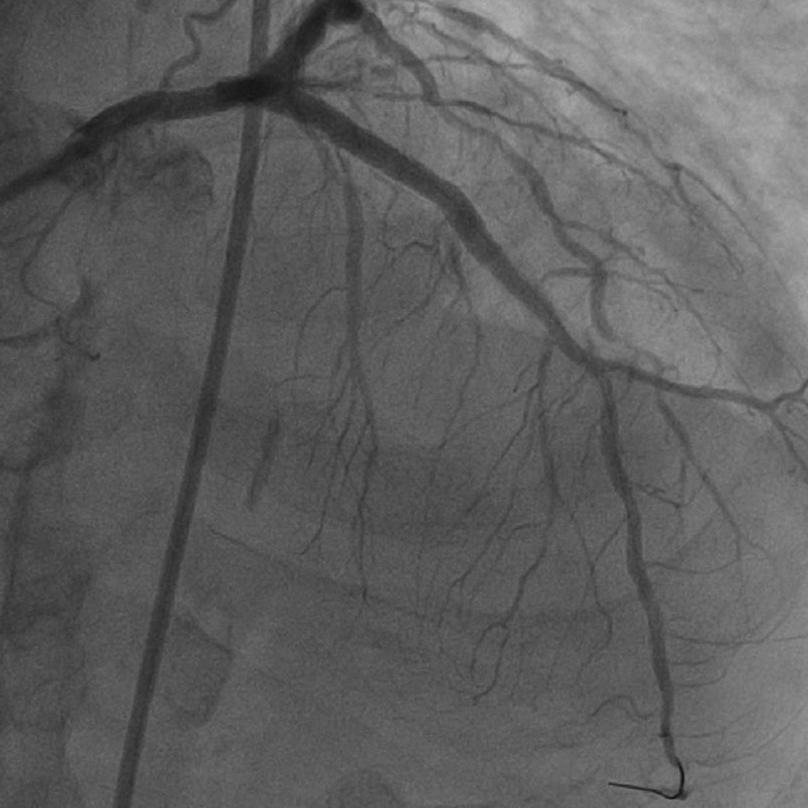

整个手术期间患者无明显不适,心电图可见一过性机械电耦合现象(属于正常现象),未见明显低血压、ST改变及持续性心律失常,复查造影及血管内超声可见前降支-左主干钙化狭窄明显改善。顺利植入两枚药物支架,复查造影及血管内超声可见支架膨胀良好,贴壁良好,术后支架内最小管腔面积达到11.45mm²,手术效果理想,术后患者胸痛症状得到明显缓解。

术后造影图像

术后IVUS影像,MSA 11.45mm²